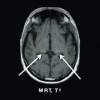

Typische MRT-Befunde sind White Matter Lesions, Schädigungen der weißen Hirnsubstanz und Pulvinar-Zeichen, die sich als Hyperintensität unter T1-Wichtung darstellen. Fabry-Patienten leben oft dauerhaft mit Schmerzen unterschiedlicher Qualität, Intensität und Lokalisierung, dies kann durch standardisierte Fragebögen, z. B. den SF-36, dokumentiert werden.

MRT, T1

mrt_01

Bilaterale Signalerhöhung im posterioren Thalamus (“Pulvinar-Zeichen”)